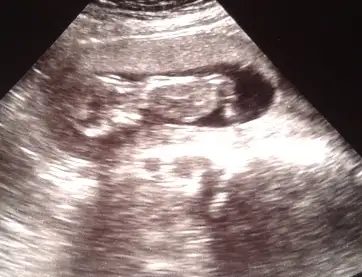

Kizlar yorum yapar kemik yapisina keseye gore..ama nub gormedim sanki ya da tecrubesizligimdennnnbenim bebeğimede bir bakarmısınız? fotografta 12+3 günlük

Senin bebikte kiza benziyobenim bebeğimede bir bakarmısınız? fotografta 12+3 günlük

Kesine yakin kiz diyorum